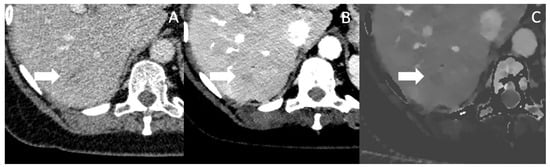

To be eligible for curative treatment absence of distant metastatic disease is mandatory. The detection of small hypovascularized liver metastases can be challenging in conventional CT imaging. A recent meta-analysis of 987 patients showed an overall pooled sensitivity for CT of 45% for detection of liver metastases [54]. Though with a high risk of bias, the results suggest a severe disadvantage compared to MRI, which is still not a part of the routine diagnostic work-up in many centers. There are different techniques in conventional CT to improve contrast, such as lowering the tube voltage or optimizing the contrast medium injection. As aforementioned, iodine attenuation is increased with approaching the iodine k-edge, VMI should also improve differentiation between hypo- or hyper-vascularized liver lesions to the healthy liver parenchyma. Another study by Nagayama et al. showed superiority of VMI over the portal venous phases in lesions <1 cm with greater visibility of metastases in energies approaching the k-edge with nearly constant noise levels abroad the spectrum from 70 to 40 keV [7].

In Figure 5, a patient with a small hypodense lesion in Segment VI is depicted in conventional, VMI and IDM, which was later affirmed by biopsy to be a PDAC metastasis. Table 2 summarizes the above discussed benefits of spectral CT for the determination of tumor extent, vascular invasion, therapy monitoring and for the detection of metastasis and shows all available studies.

Figure 5. Conventional CT imaging with a subtle, ill-defined lesion in Segment VI (marked by the arrow) (A). In Mono-E (B) and on iodine density maps (C), the lesion is still subtle visible, but more clearly demarcated and hypoattenuating, increasing the likelihood for malignancy. The lesion was histopathologically a metastasis.